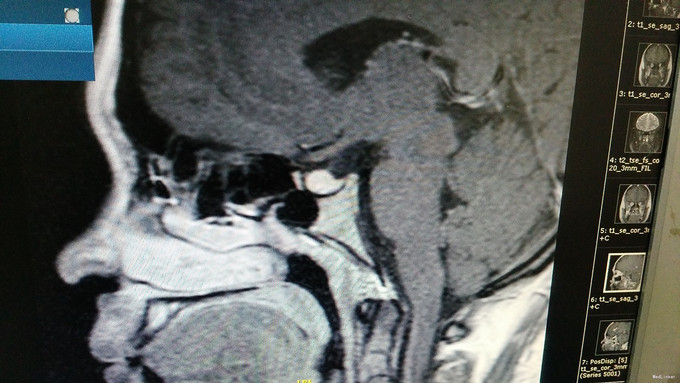

入院查体:无毛发增多,无满月脸及多血质面容,齿龈有色素沉着,可见喉结,颜面及后背可见皮肤痤疮,毛囊角化,未见明显胡须及腋毛,无颈蹼、肘外翻、双乳腺未发育。腹部未见紫纹,阴毛稀少、呈女性分布,可见阴蒂肥大呈阴茎状,外阴部仍可见尿道口。 入院后完善检查及检验: 肾上腺皮质节律: 8:00 15:00 24:00 第一天:ACTH 15.82 18.8 172.6 COR 277.6 372.7 387 第二天:ACTH 29.98 17.51 6.97 COR 478.7 227.4 57.66 第三天:ACTH 42.35 13.15 12.52 COR 547.9 179.3 62.07 血清生长激素测定GRH<0.15mIU/L。胰岛素生长样因子-1IGF-1183.00ng/ml。血清泌乳素测定PRL350.00mIU/L。促性腺激素系列:血清促卵泡刺激素测定FSH3.36mIU/mL,血清促黄体生成素测定LH9.47mIU/mL。男性激素系列:血清雄烯二酮测定AND10.80nmol/L,血清睾酮测定TES3.50nmol/L,血清游离睾酮F-TEST12.13pmol/L,血清脱氢表雄酮及硫酸酯测定DHS5.89umol/L,性激素结合球蛋白SHBG54.20nmol/L。雌性激素系列:血清孕酮测定PRG6.77nmol/L,血清雌三醇测定UE3<0.24nmol/L,血清雌二醇测定E2354.00pmol/L。阴式彩超:右卵巢囊性回声,内呈网状,盆腔积液。鞍区MR平扫+增强:垂体形态饱满,考虑垂体增生,请结合临床。肾上腺3D增强CT:左侧肾上腺结合部改变